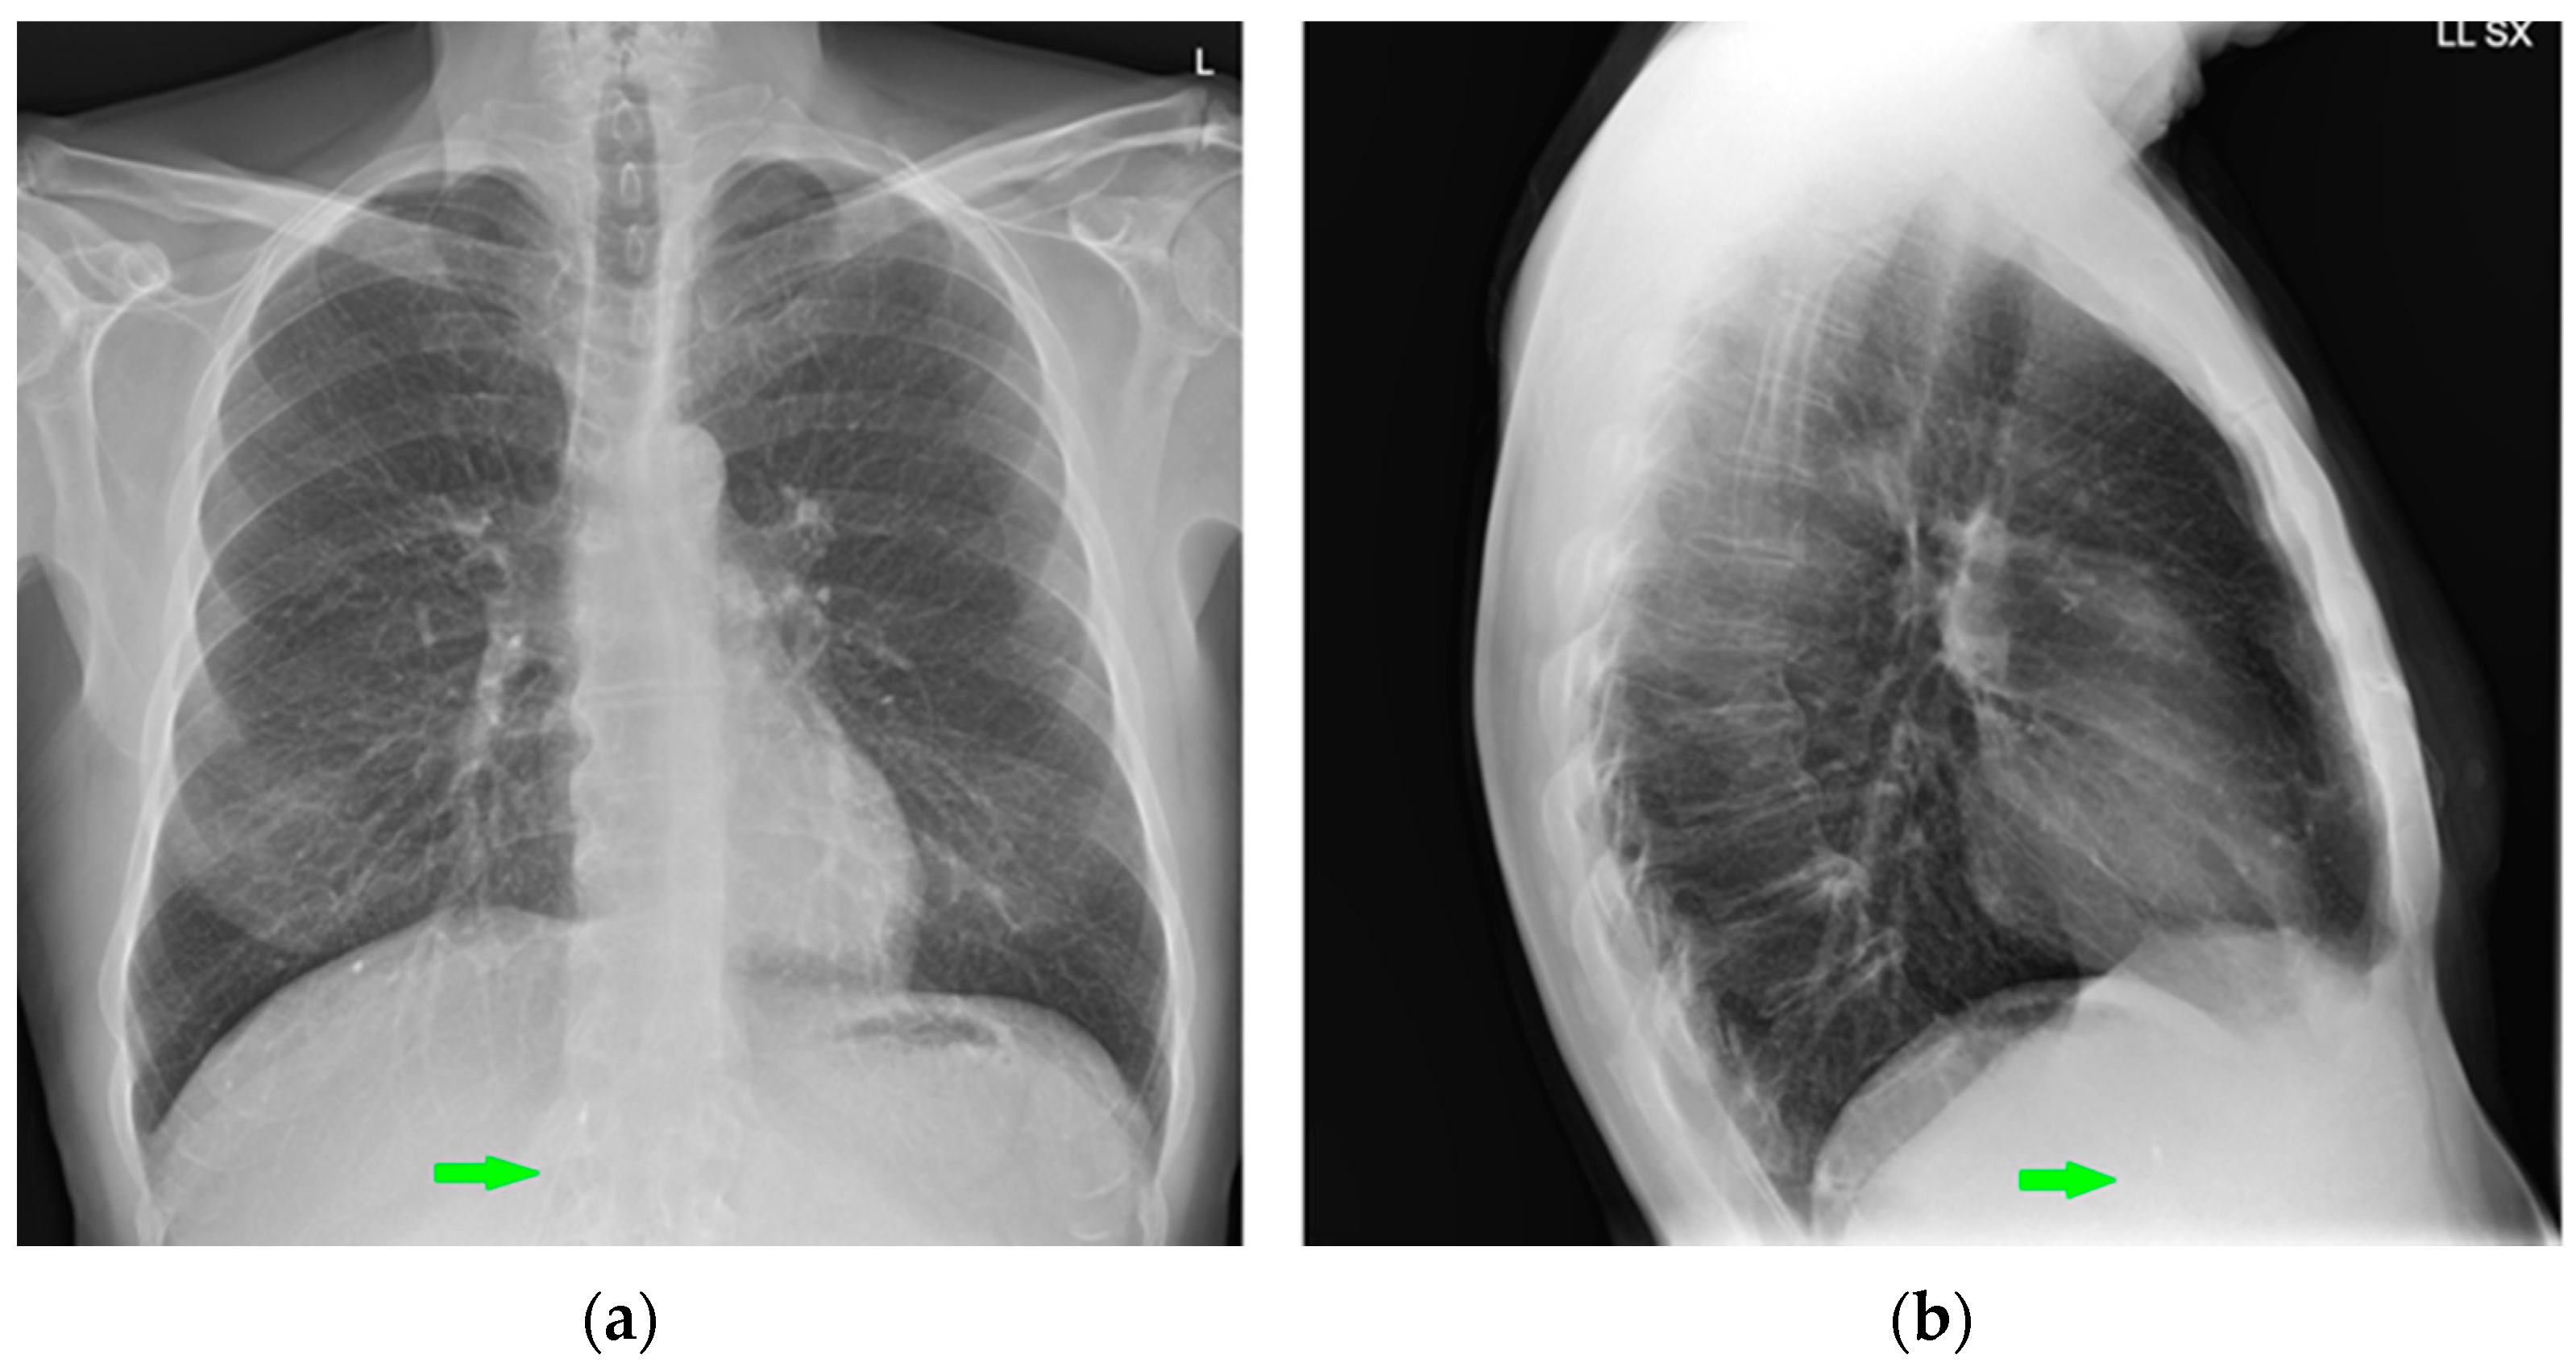

Figure 28.

Right apical chest drainage tube in patient with right pneumothorax (blue arrow) on PA (a) and LL (b) projections.